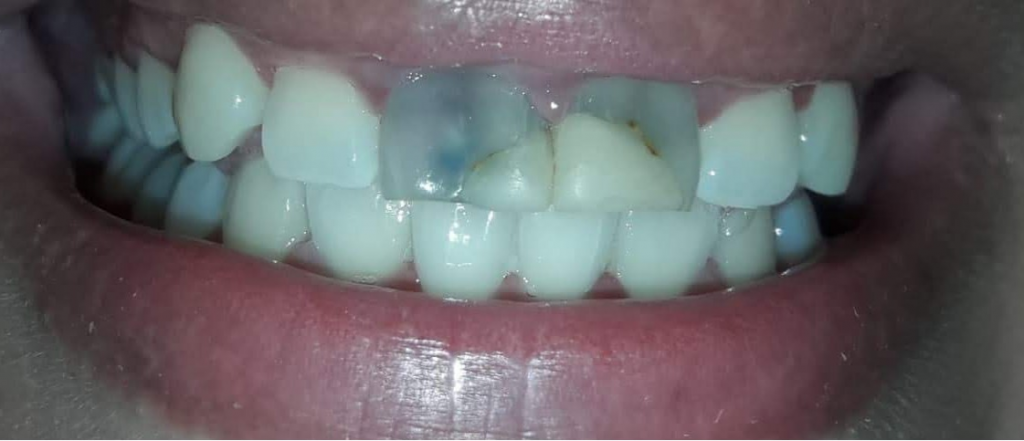

Paciente femenina de 28 años acude a la Facultad de odontología por motivo estético y molestia en el sector anterior y es derivada la asignatura Endodoncia B. Refiere alteración en la coloración de sus incisivos superiores y vergüenza al sonreír y molestia al morder con sus dientes delanteros. Al examen clínico, se observa restauración defectuosa y coronas manchadas (Fig 1-2). La paciente relata una caída hace más de 10 años, tras la cual le realizaron una reparación dental con tornillos metálicos.

Fig. 1 foto inicial Vestibular

Fig. 2 Foto inicial vest y palatina